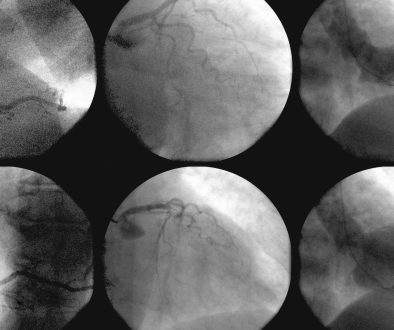

3. **التصوير والفحوصات القلبية**:

– إجراء اختبارات مثل تخطيط القلب الكهربائي (ECG)، واختبارات الإجهاد، والأشعة القلبية لإنشاء صورة واضحة للحالة الصحية للقلب.

3. **الإجراءات التداخلية**:

– إجراءات مثل تركيب الدعامات القلبية وتوسيع الشرايين يتم استخدامها لتقليل الانسداد وتحسين تدفق الدم.